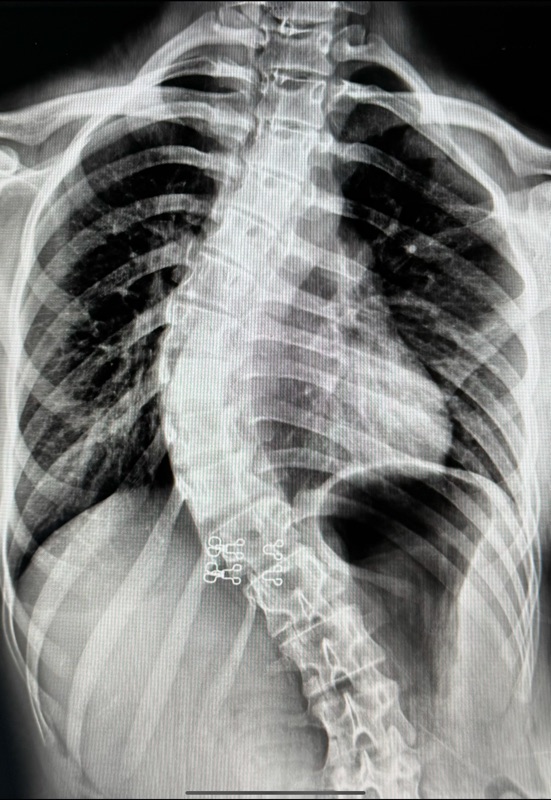

กระดูกสันหลังคด (Scoliosis) คือภาวะที่กระดูกสันหลังโค้งผิดปกติ มีลักษณะเป็นรูปตัว “S” หรือ “C” โดยส่วนใหญ่มักเกิดในวัยรุ่น โดยเฉพาะช่วงอายุ 10-18 ปี เนื่องจากเป็นช่วงที่ร่างกายกำลังเติบโตอย่างรวดเร็ว

• ปัญหาเกี่ยวกับปอดและหัวใจ: ในกรณีที่กระดูกโค้งมาก อาจกดทับอวัยวะภายใน